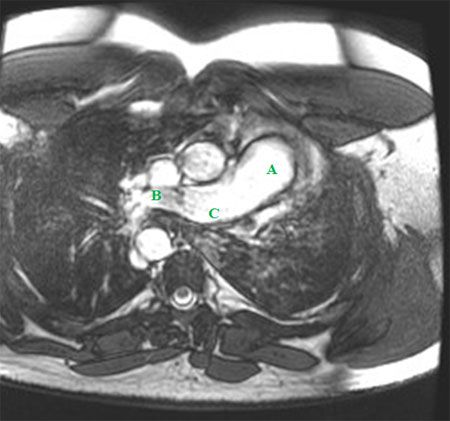

An ECG showed no significant abnormalities. A prominent right pulmonary artery, a right-sided aortic arch, cardiomegaly, and diminished left lung volumes were seen on a chest radiograph (Figure 1). An echocardiogram demonstrated normal chambers with no systolic dysfunction, no evidence of valvular or congenital heart disease, and normal pulmonary artery pressures. CT angiograms (CTAs) of the chest (Figures 2 and 3), a cardiac MRI scan (Figure 4), and a ventilation-perfusion (V/Q) lung scan (Figure 5) were also obtained. Pulmonary function tests (PFTs) revealed a moderate restrictive pattern (total lung capacity, 68% of predicted) with a mildly decreased carbon monoxide-diffusing capacity (76% of predicted) as per the ATS/ ERS task force (2005) standardization guidelines.

The CTAs showed complete absence of the left pulmonary artery, an enlarged right pulmonary artery, and a hypoplastic left lung (Figures 2 and 3). Isolated complete absence of the left pulmonary artery, an enlarged right pulmonary artery, a hypoplastic left lung, and a right-sided aorta were seen on the cardiac MRI scan (Figure 4). The V/Q lung scan showed hypoventilation of the left lung, with complete absence of left lung perfusion (Figure 5). These findings confirmed the diagnosis of isolated unilateral absence of pulmonary artery (UAPA).

Echocardiography is useful for excluding other cardiac anomalies and for screening for pulmonary hypertension. Contrast-enhanced high-resolution CT and MRI have proved valuable as well. The advantage of combined 3-dimensional cine gradient echo MRI and magnetic resonance angiography using gadolinium is that there is no radiation. Also, findings from these studies have excellent correlation with findings from cardiac catheterization and echocardiography.6 Right-sided and left-sided heart catheterization are generally used for evaluation of pulmonary hypertension.